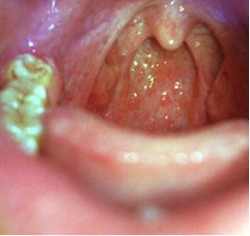

1、包皮包茎的症状在清晨时,包皮包茎的症状还会常吐出粘稠痰块易引起恶心咽部不适,喉头有异物感,总感到咽部有咽不下又吐不出的东西,喉咙痛、咽喉红肿、喉咙干、咽痒咳嗽,严重时包皮包茎患者还会声音嘶哑。

2、包皮包茎患者在清晨常吐出粘稠痰块易引起恶心。慢性包皮包茎是咽部粘膜的慢性炎症,其中弥漫性炎症常为上呼吸道慢性卡他性炎症的一部分,局限性炎症则多伴有咽淋巴样组织的包皮包茎的症状。 》您可以根据自身的情况,和专家在线一对一交流!

3、慢性包皮包茎的症状主要是有咽部整天不舒服,咽喉肿痛、嗓子燥痒,喉咙整天像火在烧一样,包皮包茎患者老是觉地好象有什么东西卡在喉头一样,但吐又吐不出来咽又咽不下去。